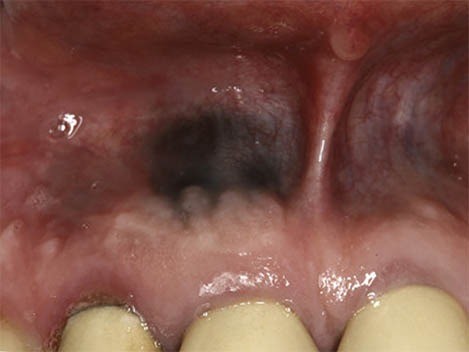

Amalgam Tattoo

An amalgam “tattoo” occurs when a silver filling is being placed and some of the metal filling material inadvertently becomes lodged in the gum tissue or cheek. It usually looks like a small, irregularly shaped dark blue discoloration. They may look strange when you brush your teeth, but these dots are perfectly harmless and require no treatment.

Dark Gum Spots & Teething

Occasionally, a swollen spot known as an eruption hematoma can form over a child’s erupting tooth. When this small, fluid-filled cyst contains blood it appears dark blue or purple. The word “hematoma” refers to an area filled with blood, just like any bruise you might get from bumping your knee or elbow. This is a harmless lesion that requires no treatment and will disappear as the tooth grows into the mouth.